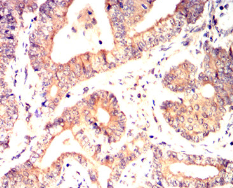

IHC    1/200 - 1/1000